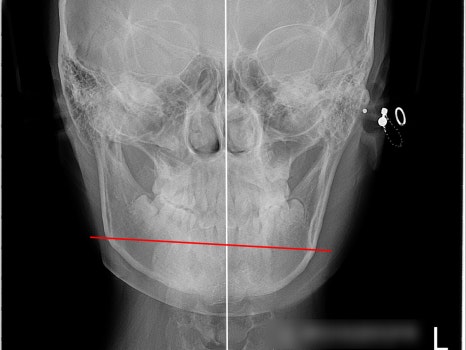

그런데 이번 케이스의 경우

아래턱이 오른쪽으로 치우져진 상태라,

오른쪽 어금니부터는

거꾸로 물리는 반대교합이 관찰되고

교합이 어딘가 불안정해 보였습니다.

이를 전문 용어로

‘횡적 부조화(transverse discrepancy)’라

합니다.

또한 오른쪽 작은 어금니 하나가

결손된 상태였는데

이 또한 비대칭, 부정교합을

유발하는 원인이 되었습니다.